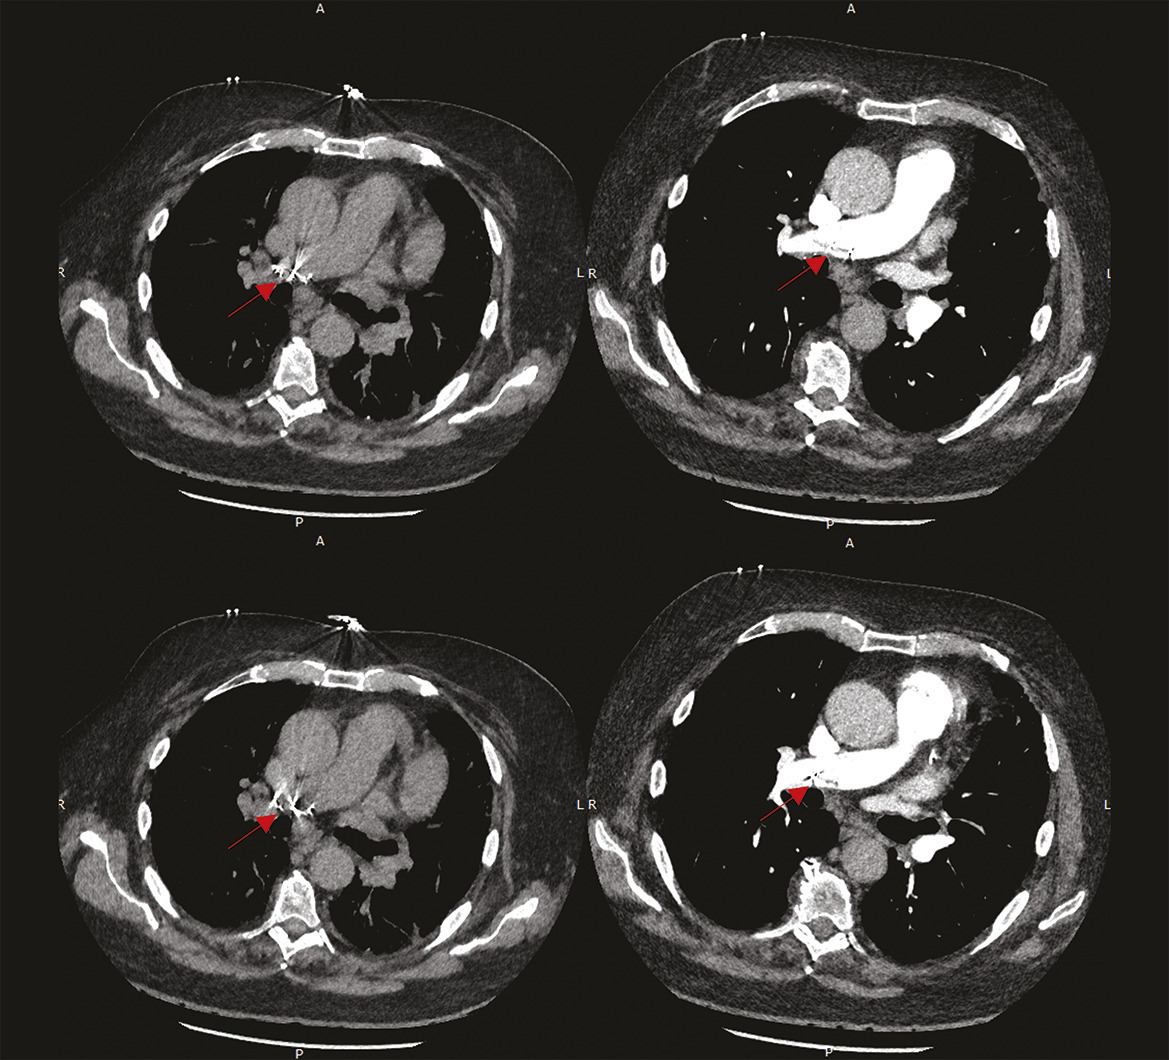

Ce patient de 74 ans consultait en raison de l’apparition depuis quelques jours d’une dyspnée d’effort sans douleur thoracique. Il avait pour antécédents une cardiopathie ischémique, une hypertension artérielle et la fermeture par voie percutanée d’un foramen ovale perméable par une prothèse d’Amplatz qu’on savait incomplète depuis quelques années. Cliniquement, on notait des signes de détresse respiratoire avec une polypnée à 18 cycles/min et une désaturation nécessitant la mise sous 4 L/min d’oxygène. L’auscultation était claire et symétrique. L’électrocardiogramme montrait un rythme sinusal régulier à 92 BPM avec un bloc de branche droit connu, sans signes d’ischémie. La mesure des gaz du sang en air ambiant montrait une hypoxie à 56 mmHg, une hypocapnie à 24 mmHg et un pH normal. Un angioscanner, à la recherche d’une embolie pulmonaire, (figure ) montrait une migration prothétique dans l’artère pulmonaire droite. Le patient était transféré vers un plateau de chirurgie cardiaque en urgence.

La migration d’une prothèse de fermeture d’un foramen ovale perméable est rare et survient principalement de manière précoce ou perprocédurale.1, 2 La prothèse peut se trouver dans différents sites : cavité cardiaque, crosse de l’aorte, voire aorte abdominale ou artère pulmonaire. La migration résulte le plus souvent de facteurs anatomiques qui limitent le bon positionnement des ailettes du dispositif : anévrisme septal, septum secundum épais, long tunnel de circulation du sang dans le foramen ovale. Un choix inapproprié de taille prothétique favorise aussi son instabilité positionnelle tout comme la persistance d’un shunt. En fonction de la symptomatologie du patient (dyspnée, état hémodynamique, intensité du shunt après la réouverture du foramen) et de la faisabilité technique (position du dispositif, risques de lésions secondaires des tissus vasculaires, de surmigration, de rupture prothétique), le dispositif peut être retiré par voie percutanée ou chirurgicale.